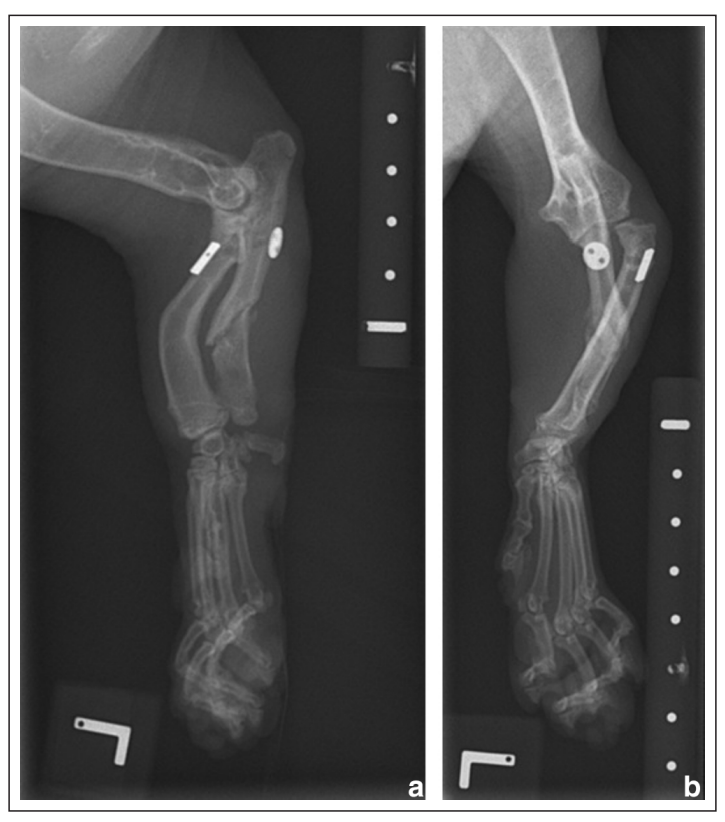

↑ 左(ac)和右(bd)前肢的正侧位和头尾位X光片。双侧桡骨头半脱位,桡骨弯曲,尺骨短小,远端尺骨生长板过早闭合,尺骨呈内翻畸形。这些变化与软骨发育不良、双侧肢体弯曲畸形、肘关节发育不良以及随后的发育型I桡骨头半脱位以及肱尺关节半脱位相符合,左侧稍显严重。